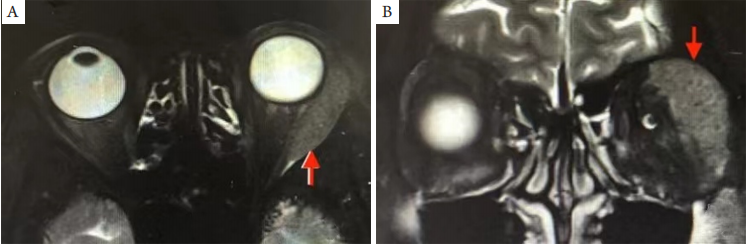

2.3 泪腺型

原发于泪腺的MALT淋巴瘤,可一侧或双侧发病,约15%为双侧[3-5,13,17-18]。患者临床表现是上睑外侧肿胀隆起,上睑中外侧触及质地柔软肿大的泪腺。影像学表现为泪腺炎症样肿大,范围多以外直肌及上直肌为界,较少突破肌锥内间隙,病变在轴位上呈“杏仁样”(图3A),冠状位上呈“月牙形或半月形”改变(图3B)。

部分患者可合并耳前和颌下淋巴结肿大,亦可合并血清IgG4升高。

20230619102530_7858.png

图3 泪腺区原发性 MALT淋巴瘤MRI

Figure 3 MRI shows the primary MALT lymphoma of lacrimal gland

(A)轴位MRI示左泪腺肿大向后蔓延,T2WI等信号;(B)冠状位MRI示泪腺呈半月形肿大,T2WI等信号。箭头示病变部位。

(A) Axial MRI shows left lacrimal gland enlargement spreading backward, T2WI isosignal; (B) Coronal MRI shows half-moon enlargement of lacrimal glands, T2WI isosignal. Arrows indicate the lession.